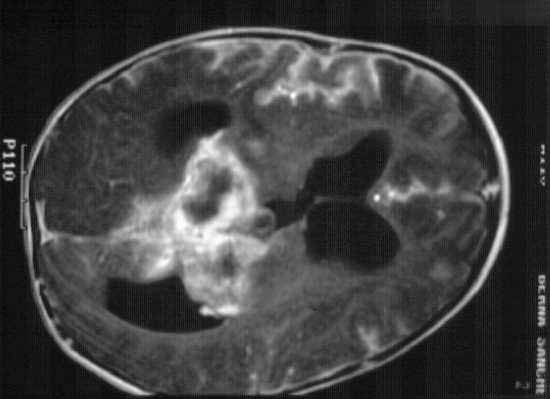

ICONOGRAFÍA

fig. 1

Figura 1

fig. 2

Figura 2

fig. 3

Figura 3

fig. 4

Figura 4

fig. 5

Figura 5

fig. 6

Figura 6